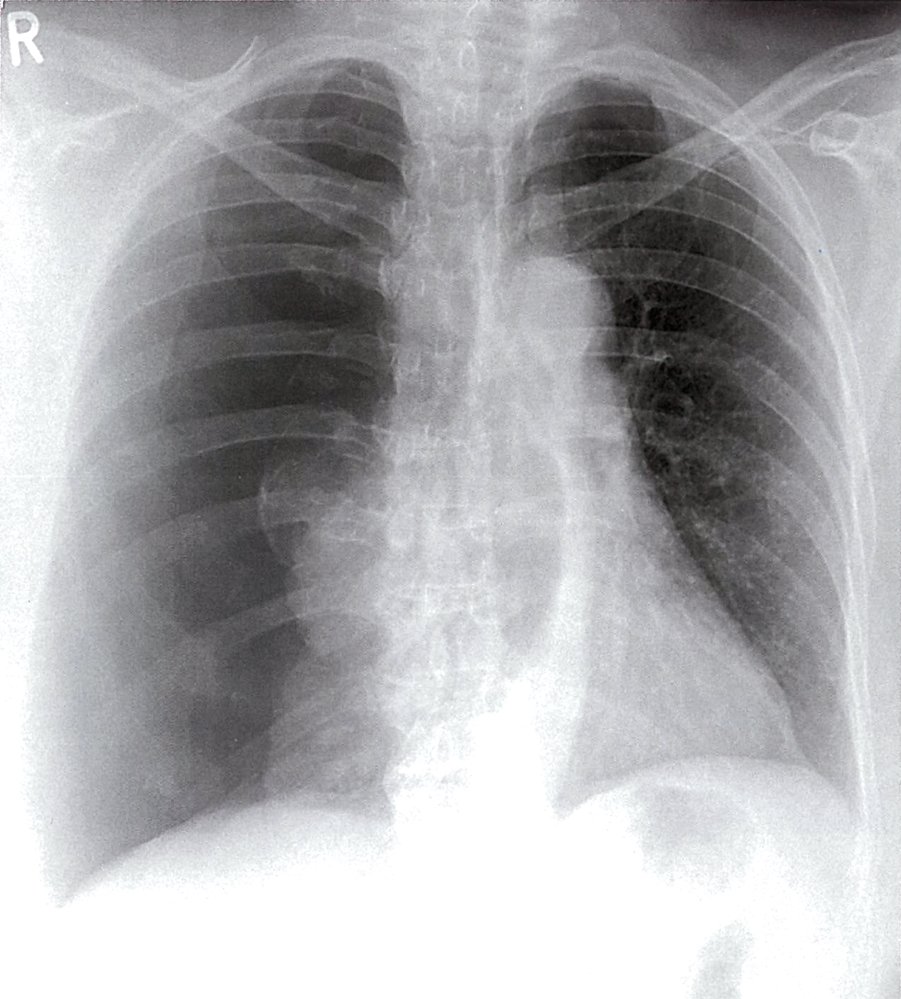

Chest x-ray and/or lung ultrasound

Chest x-ray